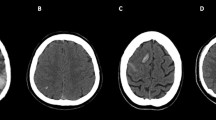

On the first available acute NCCT performed at symptoms’ onset, image-based classification systems were designed considering the topographic distribution of intracranial lesions (unilateral vs. bilateral thalami; edema in basal ganglia and other brain regions; parenchymal and ventricular hemorrhage), mass effect (midline shift), and hydrocephalus development. The Intracranial Imaging Score (IIS) was developed, assigning 1 point for each item, and the Venous Occlusion Imaging Score (VOIS) was developed, considering major venous dural sinuses, deep veins system, and cortical veins involvement, assigning either 1 or 2 points for unilateral or bilateral absence of contrast opacification on CeCT (Table 2; Fig. 1). Higher scores indicated a severer neuroradiological involvement.

Brain CT features in patients with venous system thrombosis. Axial unenhanced CT (a–j); enhanced CT (k–n). Intracranial changes. (1) Topographic distribution of parenchymal density changes: unilateral thalamus edema (left-side hypodensity, arrow in a); thalami edema (bilateral hypodensity, arrows in b); unilateral thalamus and basal ganglia edema (left-side hypodensity, arrows in c); thalami and basal ganglia edema (bilateral hypodensity, arrows in d); other parenchymal venous strokes (left temporal edema, arrow in e). (2) Hemorrhage: unilateral parenchymal hemorrhage (arrow in f); bilateral parenchymal hemorrhage (arrows in g); intraventricular hemorrhage (arrowhead in g). (3) Mass effect: midline shift (h); hydrocephalus (asterisks in i, j). Venous system occlusion. (1) Dural sinuses thrombosis (DST): unilateral (arrow in k) or bilateral (arrows in l) transverse and sigmoid sinuses involvement. (2) Deep cerebral veins thrombosis (DCVT): unilateral (arrow in m) or bilateral (arrows in n) cerebral internal veins involvement